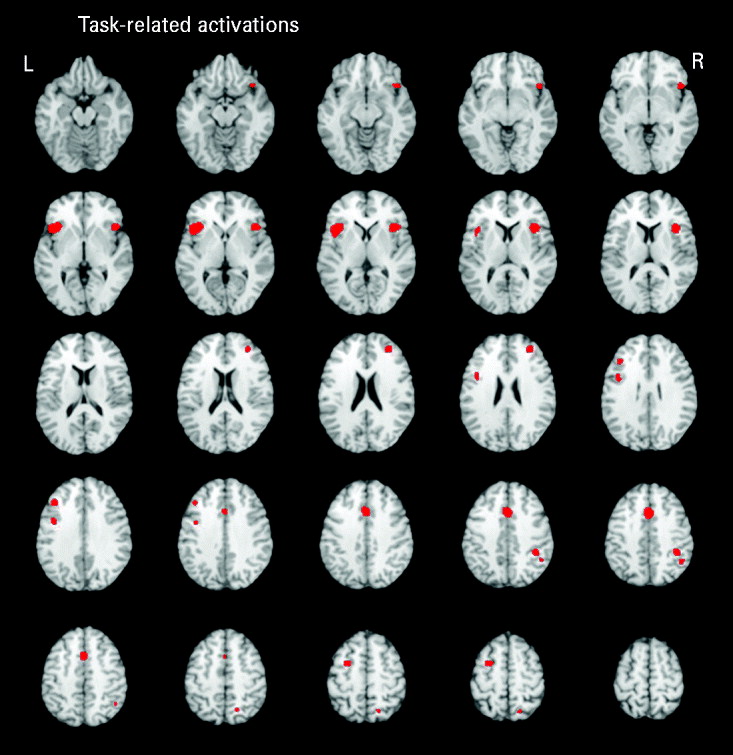

Executive functioning task-related activations

Five studies reported executive functioning task-related activity combined across relatives and control groups. Robust activations were found in 10 clusters, encompassing the bilateral middle frontal (BA 9/10), bilateral inferior frontal (BA 9/47), anterior cingulate (BA 32), bilateral insula (BA 13), left precentral (BA 6), right inferior parietal (BA 40) and right superior parietal (BA 7) regions (see Fig. 1).

Fig. 1. Above-threshold brain activations associated with executive functioning for both the control and relative groups combined. L, left; R, right.